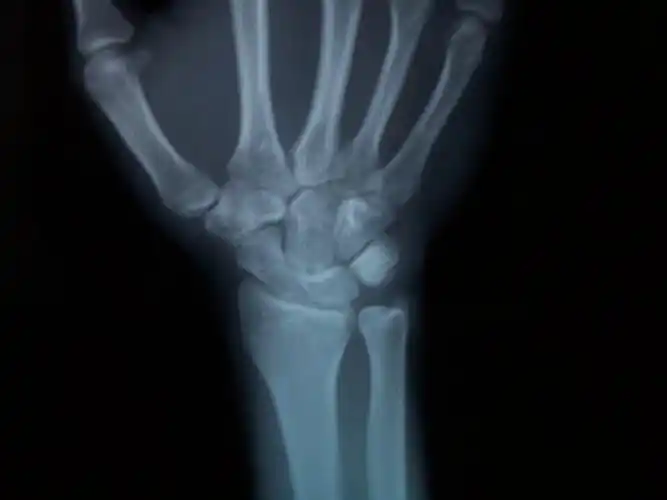

问:右手手腕下尺桡关节间隙宽,之前医院检查绑过一个月石膏!

骨科专家进~~关于下尺桡关节脱位

月骨和尺骨头是否有影像学改变,月三角间隙是否正常,远尺桡关节(druj)

请问这是下尺桡关节脱位吗